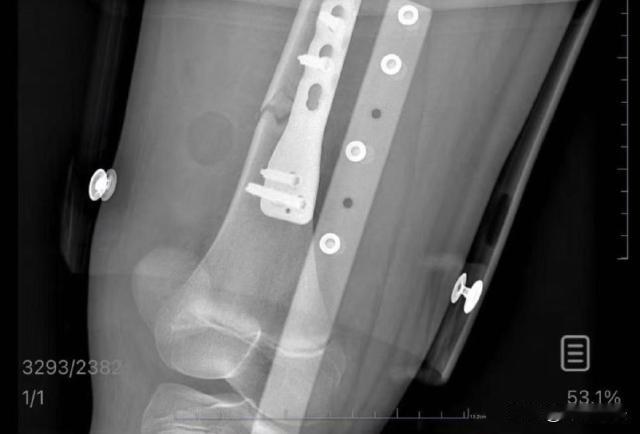

无锡,一位妈妈带着孩子出发去杭州,快到无锡站的时候,上铺一位男子下来,自己没有抓稳一下子摔倒在孩子腿上。10岁小姑娘疼的哇哇哭,列车人员赶紧过来帮忙救助。随后,这名男子陪着母女俩来到无锡儿童医院治疗,做完手术之后,男子称要去筹钱,然后人就消失无影踪。妈妈称,也不知道孩子后面是否会有后遗症,但是男子的态度让自己十分心寒。 新闻夜航10月5日报道了这个新闻。目前,女孩妈妈一直没有联系上这位肇事男子,妈妈称会考虑走司法途径,一定要给自己的女儿维权到底。 8月24日,朱女士带着自己十岁的女儿,从老家出发前往杭州旅行。二人购买的是下卧铺,上卧铺是一位高大的男乘客。 母女俩躺到卧铺上准备休息时,这个时候,上卧铺的男子开始有动静。他准备下来了,但是却一个不小心,没有抓稳扶手,一个踉跄就摔倒。 当时,这位男子正好就摔到了下铺女孩的腿上。摔倒之后,女孩子发出了剧烈的尖叫声,一直在喊疼。朱女士赶紧安慰女孩,但是孩子还是哭的撕心裂肺。 当时动静比较大,惊到了巡回的列车员。列车员赶紧来到现场查看情况,看到一名小女孩正在哭泣。了解情况之后,列车员建议赶紧给孩子送往医院救治。 列车前方到站无锡站,到站之后,工作人员帮助喊来了救护车,及时将小女孩给送到了无锡儿童医院。当时一起前往医院的,还有那名肇事男子。 到医院治疗之后,医生诊断出,孩子的右股骨骨折,而且还有部分断裂,必须要立即进行手术。听到孩子需要做手术,男子称自己会帮忙垫付住院押金。 付完押金之后,男子也去帮忙给孩子购买了住院护理用品。然而,孩子做完手术之后,第二天,朱女士再跟男子联系的时候,男子称自己手里没钱了,准备回老家去筹钱。 当时男子也就口头说回家筹钱,之后再也没有跟朱女士联系过,也没有再关注孩子的情况。直到九月初,朱女士终于打通了男子的电话,男子就说让朱女士把住院的收费清单发给他。 当朱女士把住院清单发送过去之后,这位男子就彻底消失了。朱女士说,给他打电话,他不接,而且后面干脆就打不通了。就连发短信,他也不再回复自己了。 朱女士表示,自从受伤之后,女儿吃饭、上厕所、学习,全都是平躺在床上,而且孩子情绪低落,每天都过的不开心。 虽然手术是成功的,但是后期的康复治疗,是一个非常漫长的过程,医生也表示不清楚孩子后期是否会有后遗症。肇事男子的确不是故意的,朱女士也表示谅解,但是现在逃避责任,这个态度让自己实在无法接受。 朱女士决定为自己女儿维权,现在她把事情经过都告知了媒体,而媒体记者也帮忙拨打了男子的电话,但是这名男子仍然没有接听。 无奈,朱女士称,后续她会上诉,一定要追究这位男子的法律责任,也一定要为自己的女儿维权到底。 1.如果列车上没有做好安全保障措施,导致他人摔倒,并且造成他人损害,列车部门是否需要承担法律责任呢? 根据《民法典》第八百二十三条规定,承运人对运输过程中旅客的伤亡承担赔偿责任,除非伤亡是由旅客自身健康愿意或者故意、重大过失造成。如果列车没有采取防滑措施、没有及时清理障碍,均可能被认为未尽到安全保障义务。 如果旅客自身存在过失,如没有扶稳、奔跑等,自己不小心摔倒,则可以减轻列车部门责任。本案中的男子,就需要承担70%的安全责任,列车部门需要承担30%的安全责任。 2.男子摔倒之后压到女孩子,导致女孩子腿骨断裂,他需要承担怎样的责任呢?如果逃避责任,拒绝面对面处理问题,男子要被法律惩处吗? 根据《民典法》规定,行为人摔倒压到受害人导致其腿骨断裂,行为人需要承担女孩的医疗费、护理费、营养费以及后续的治疗费用。 男子自己也承认会去担责,但是自己手里钱不够,因此会回去筹钱。但是直到最后,男子也没有回来承担医疗费用。男子的行为可能涉嫌违法。 根据《刑法》第133条规定,行为人造成他人人身伤害,却逃逸试图逃脱责任。行为人的行为可能构成逃逸罪,会被处以3-7年有期徒刑。 该男子造成女孩受伤之后,称自己要去筹钱于是离开,离开之后,孩子妈妈再也没有联系上他。这位男子属于逃逸行为,拒绝对自己的过错负责。因此,后期这位男子极有可能会面临刑事处罚。 作为成年人,行为处事需要小心谨慎,犯错之后也要为自己的举动买单。如果逃逸,拒绝负责,“法”网不会轻易任其逃脱。 对于本案,大家都作何看法呢。